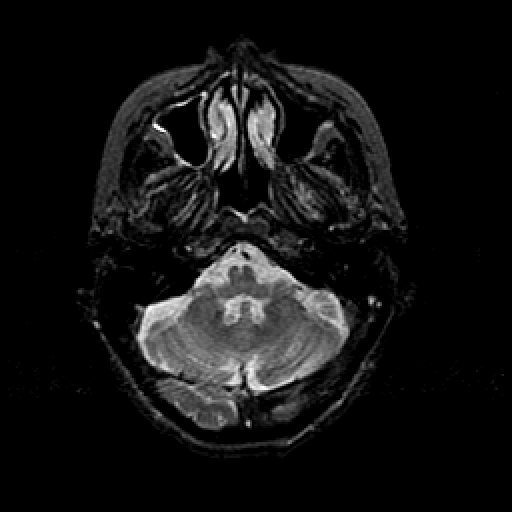

T2-weighted structural MR: Slice 12

Slice 12